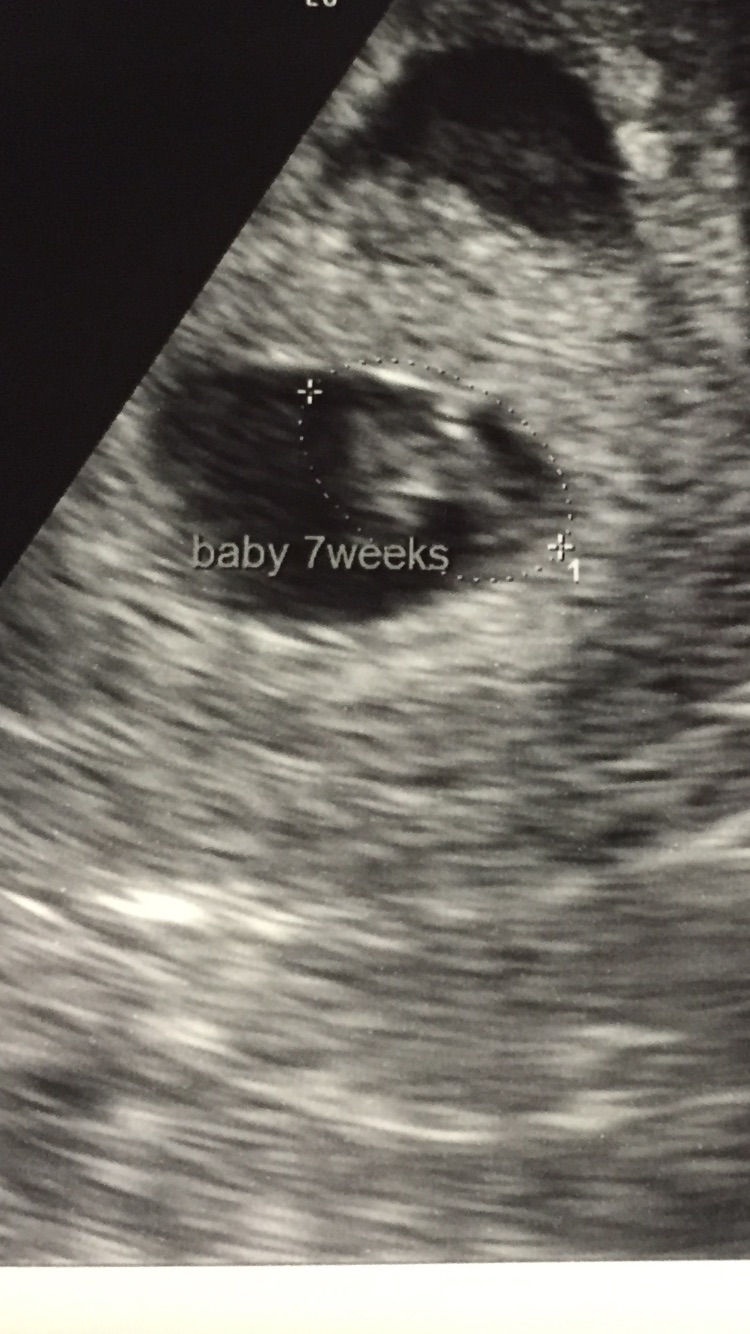

Then the next ultrasound was this past Monday (10 weeks 6 days) and baby was so big! Sleeping at first and then made the meanest face when the tech woke baby up! My husband and I loved it!